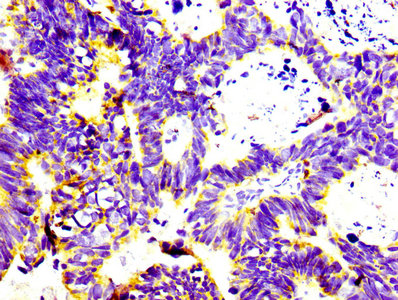

除正常免疫细胞外,CD74 在多种肿瘤中也呈高表达。例如,在多发性骨髓瘤中,CD74 mRNA 可在几乎全部新诊断患者的 CD138+ 浆细胞中检测到 [5];在多种淋巴瘤中,CD74 也具有较高表达频率,包括霍奇金淋巴瘤、B 细胞淋巴瘤、结外 NK/T 细胞淋巴瘤和成熟 T 细胞淋巴瘤等 [4]。这种广泛表达使其成为潜在的治疗靶点 [5, 6]。

CD74 在恶性肿瘤中具有多重作用,包括促进肿瘤细胞生存、参与肿瘤微环境塑造、驱动融合基因相关肿瘤发生,以及介导治疗耐药。其在血液系统肿瘤中表达尤为广泛,霍奇金淋巴瘤、B 细胞淋巴瘤、结外 NK/T 细胞淋巴瘤、成熟 T 细胞淋巴瘤和浆细胞骨髓瘤中均可见较高表达 [4]。在多发性骨髓瘤中,CD74 几乎普遍表达,为靶向治疗提供了明确依据 [5, 15]。

在实体瘤中,CD74 同样具有重要意义。例如,在胰腺导管腺癌中,CD74 敲低可抑制肿瘤细胞增殖、迁移和侵袭,并减少 S100A8/S100A9 分泌,从而影响促炎性肿瘤微环境 [14]。在肺癌和胰腺癌中,CD74-NRG1 融合是重要致癌事件,能够激活 ERBB2:ERBB3 信号并驱动肿瘤进展 [13]。此外,在 ROS1 或 ALK 融合阳性肿瘤中,CD74 上调还与 TKI 耐药相关,提示其参与药物耐受细胞维持和肿瘤适应性演化。

在肿瘤微环境层面,MIF-CD74 轴被认为是重要的免疫抑制机制。在宫颈癌中,CD74 上调限制肿瘤相关巨噬细胞吞噬功能并促进 M2 极化 [16];在 LUAD 中,MIF-CD74 相关免疫抑制特征与较差生存显著相关 [8]。但另一方面,高 CD74 表达又与部分实体瘤中更"炎性"的免疫微环境及对 PD-1/CTLA-4 双抗治疗的较好反应相关 [17]。这提示 CD74 在肿瘤免疫中的作用具有明显的背景依赖性。